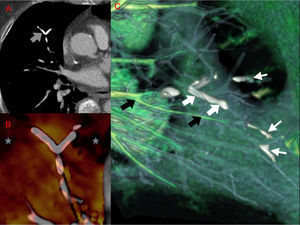

The CT pulmonary angiogram showed high-density images in the subsegmentary pulmonary branches (Fig. 1A) and in the azygos vein (adjacent to the treated vertebrae). Perfusion reconstructions with iodine and vascular mapping were used to differentiate areas of hypoperfusion (Fig. 1B) and cement embolism from endovascular iodine (Fig. 1C).

Dual-energy computed tomography after the administration of intravenous iodinated contrast medium. (A) Axial image revealing a high-density branched linear image in a subsegmentary artery in the medial segment of the middle lobe (gray arrow) suggestive of cement embolism. (B) Iodine perfusion map revealing areas of hypoperfusion (gray stars) distal to the dense linear lesion described previously. (C) Vascular map showing vessels containing iodine colored green (black arrows) and filling defects attributable to the cement in white (thick white arrows). Note how this kind of reconstruction can be used to identify a greater number of small caliber vessel defects (thin white arrows).